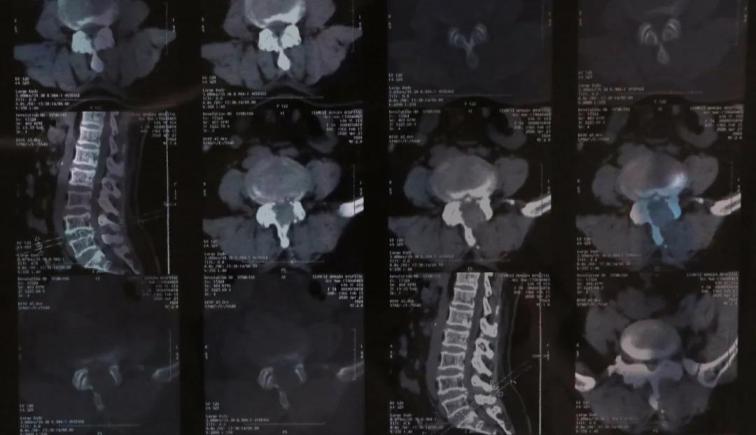

患者,女性,54歲,腰部疼痛伴雙下肢傳導(dǎo)痛五年,近半年癥狀逐漸加重,行走300米左右后疼痛難忍,生活質(zhì)量受到嚴(yán)重影響,多地醫(yī)院保守治療無(wú)效,來(lái)我院骨科,與患者交流病情后,為患者行脊柱內(nèi)鏡下單側(cè)入路雙側(cè)減壓(ULBD)椎管擴(kuò)大成型術(shù)。

術(shù)后患肢癥狀明顯減輕,功能恢復(fù)良好,下肢疼痛癥狀消失,左足背麻木感較術(shù)前明顯減輕,行走距離明顯增加。